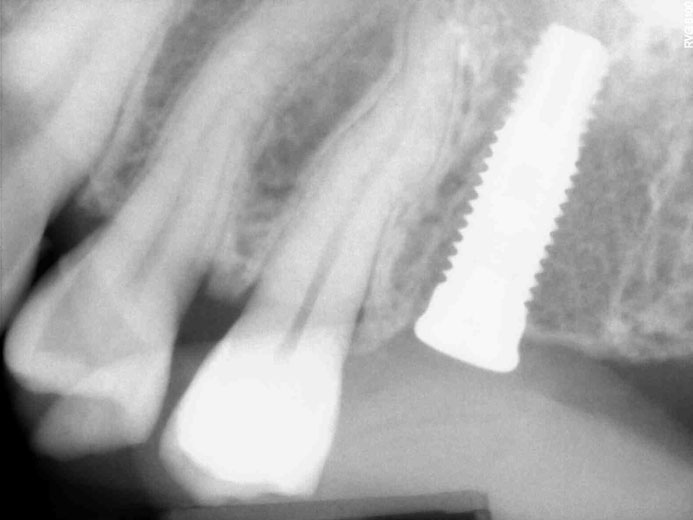

Διάγνωση και θεραπευτική αντιμετώπιση περιεμφυτευματίτιδας

Η περιεμφυτευματίτιδα είναι η απώλεια οστού γύρω από τα εμφυτεύματα. Οφείλεται σε παρόμοιες αιτίες με την περιοδοντίτιδα, ωστόσο στην περίπτωση της περιεμφυτευματίτιδας η κακή στοματική υγιεινή του ασθενούς διαδραματίζει σημαντικότερο ρόλο. Επίσης η καταστροφή του οστού είναι ταχύτερη γύρω από τα εμφυτεύματα, κάτι το οποίο οδηγεί ακόμα και σε απώλειά τους. Η συνήθης θεραπεία της περιεμφυτευματίτιδας είναι η χειρουργική πρόσβαση για καθαρισμό των ιστών γύρω από το εμφύτευμα και τα οστικά μοσχεύματα για την αντικατάσταση των οστικών ελλειμμάτων.